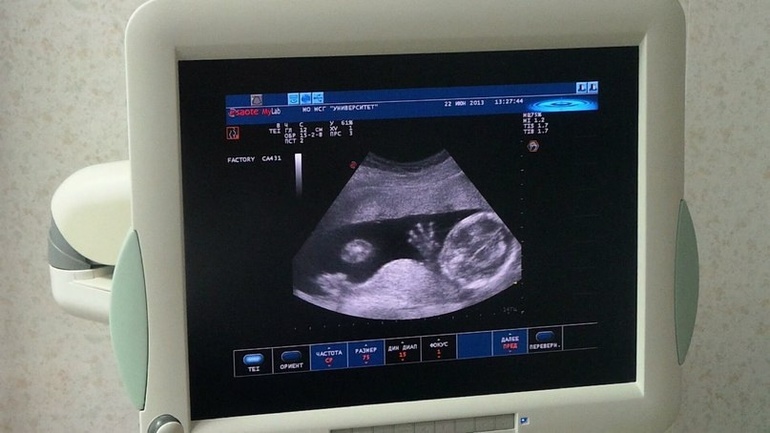

А это узи нашей малышки 22 июня)) она мама с папой машет

катя,зачем волосы обрезала??в июне вон какие локоны на свадьбе!!!с узи фото оч.здоровское!!!как вы так словили ладошку прям класс))

Волосы были нарощенные) очень тяжело было ухаживать((( Это скрин шот с видио)) так то она у нас шустрая) не сфоткаешь)))